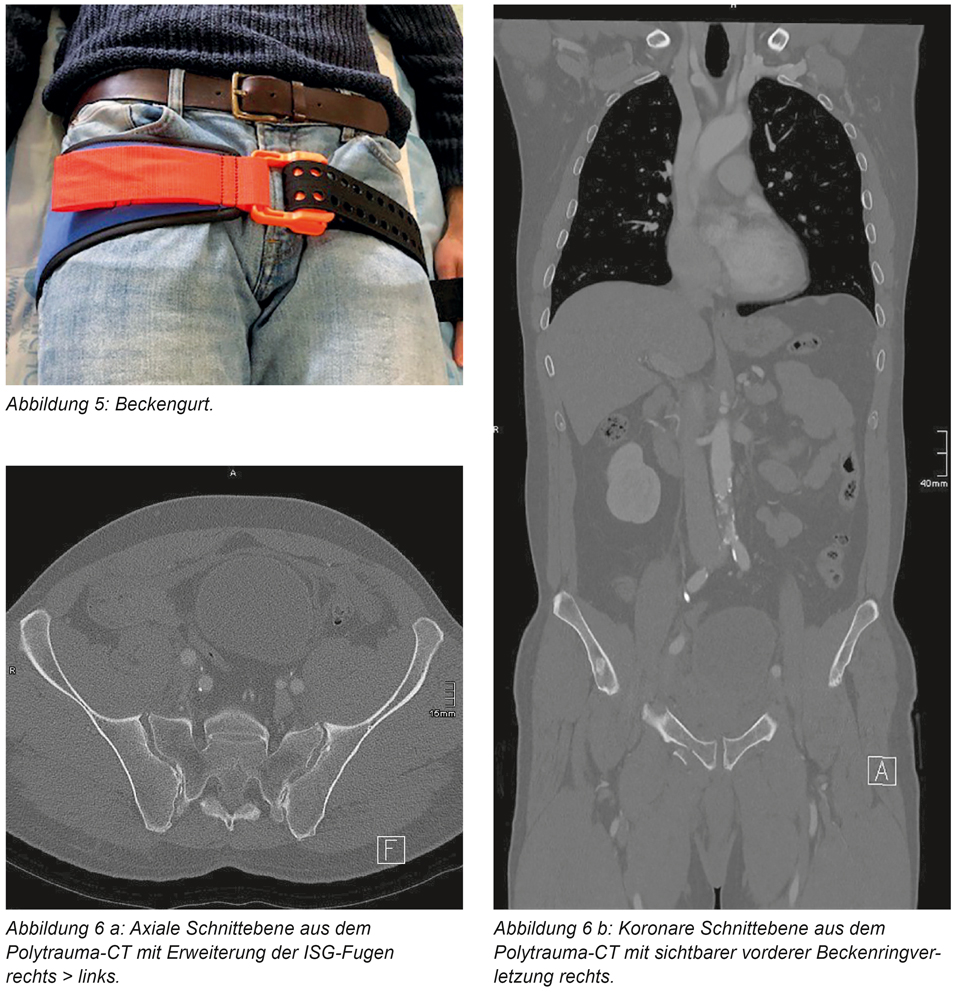

Ein 60-jähriger Motorradfahrer erleidet einen Unfall und wird analgosediert, aber wach, in den Schockraum unserer Klinik eingeliefert. Bei Verdacht auf Beckentrauma wurde vom Notarzt am Unfallort ein Beckengurt zur temporären Stabilisierung des Beckens bei Verdacht auf Beckenverletzung angelegt (Abbildung 5). Die durchgeführte Traumaspirale zeigt, neben Unterschenkelfrakturen, beidseits eine Beckenverletzung mit Fraktur des oberen Schambeinastes und auffälliger Weite der Ileosakralgelenk-Fugen (ISG-Fugen) beidseits (Abbildungen 6 a und b). Da die Traumaspirale mit Beckengurt durchgeführt wurde, erfolgte anschließend noch eine konventionelle Beckenübersichtsaufnahme mit geöffnetem Beckengurt. Hier zeigte sich das volle Ausmaß der Verletzung im Sinne einer Beckenring-C-Verletzung mit einer „Open-Book-Verletzung“ des vorderen Beckenrings und beidseitiger hinterer Instabilität mit Symphysensprengung (Abbildung 7). Der Beckengurt wurde sofort wieder verschlossen und der Patient notfallmäßig in den OP verbracht. Im Sinne des Damage-Control-Prinzips erfolgte nun die Anlage eines supraazetabulären Beckenfixateurs zur primären notfallmäßigen Stabilisierung. Drei Tage später erfolgte die definitive Stabilisierung des Beckens mit beidseitiger ISG-Verschraubung dorsal und einer Sechs-Loch-Symphysenplatte (Abbildungen 8 und 9), welche über einen minimalinvasiven Zugang laparoskopisch eingebracht wurde. Der aus der Hernienchirurgie bekannte Zugang ist dabei die minimalinvasive Variante des für die offene Technik verwendeten modifizierten Stoppazugangs (Abbildung 10). Dafür benötigt man insgesamt drei Portalzugänge à ca. 2 cm Länge. Die Operation wird mit den üblichen laparoskopischen Instrumenten durchgeführt. Die benötigte Platte kann über eines der distalen Portale eingeführt werden.